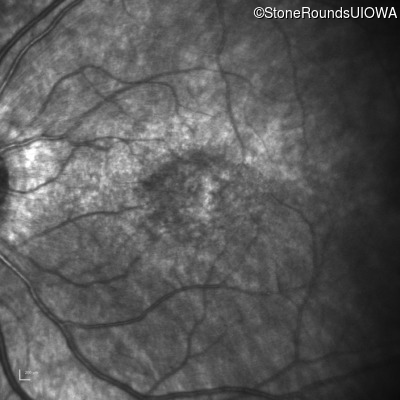

Infrared Fundus Photograph - Right - 20/80

Exemplar

Infrared Fundus Photograph - Left - 20/200